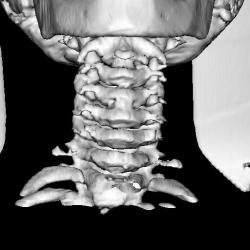

Ребенок 6 лет. Жалобы на выраженные боли в шейном отделе позвоночника. Со слов матери, боли в шее беспокоили длительное время. 2 недели отмечалась незначительная травма - девочка резко повернула голову в сторону, боли в шее услились. В настоящий момент  отмечаются выраженные боли в шее, резкое ограничение движений, повышение температуры тела, воспалительные изменения в анализах, (возможно, связанные с пиелонефритом, который также имеет место). Поступала с направительным диагнозом "ротационный подвывих атланта", однако данные рентгенографии заставили расширить круг диагностического поиска.Родовую травму мать отрицает. Хотелось бы узнать мнение уважаемых коллег.

Уважаемая коллега! С точки зрения классической рентгенологии (с учётом качества представленных снимков) могу высказать следующее:

- определяется выраженный антелистез тела С5;

- двуконтурность тел С3 и С5 может свидетельствовать о нарушении целостности костной ткани указанных тел позвонков;

- безусловно, межпозвонковые диски "поехали".

Вижу ещё раздвоенный axis.

Аксис не раздвоен, это нормальная картина для шести лет, просто верхушка зуба еще хрящевая.

Спасибо. Буду знать. По заданной теме: не хотелось бы быть освистанным, но смею предположить ювенильный ревматоидный артрит.

Случай помню. Закончилось все на удивление просто - после недели вытяжения петлей Глиссона боли ушли, движения в ШОП восстановились в полном объёме. Рентгенологические данные расценили как врожденную аномалию развития. Воспалительные изменения в анализах - как проявления пиелонефрита. В любом случае, из нашего поля зрения ребёнок ушел к нефрологам.